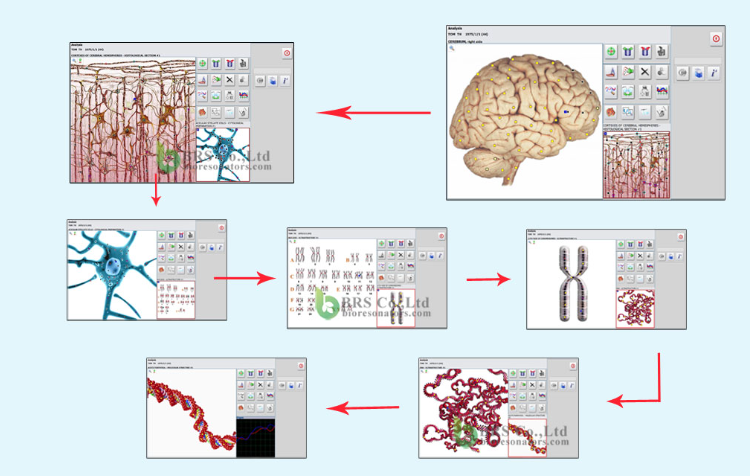

Високо ниво на визуализация: позволява в момента на изследването да се види точното местоположение на проблема

Модерно технологично ниво на Биофилия

Технологията за улавяне на честотното трептене се разработва от години като част от енергийната медицина. Знаем, че всяка клетка трепти на определана честота.

Методът, който използва “ Биофилия“ е биофизичен. Специални импулси идващи от 8 сензорна камера на апарата, въздействат на нашето тяло. Тези импулси поемат информация от тялото и я използват за тестване и установяване на здровословното състояние.

Нови технологични открития осигуряват надеждни процеси на диагностика.